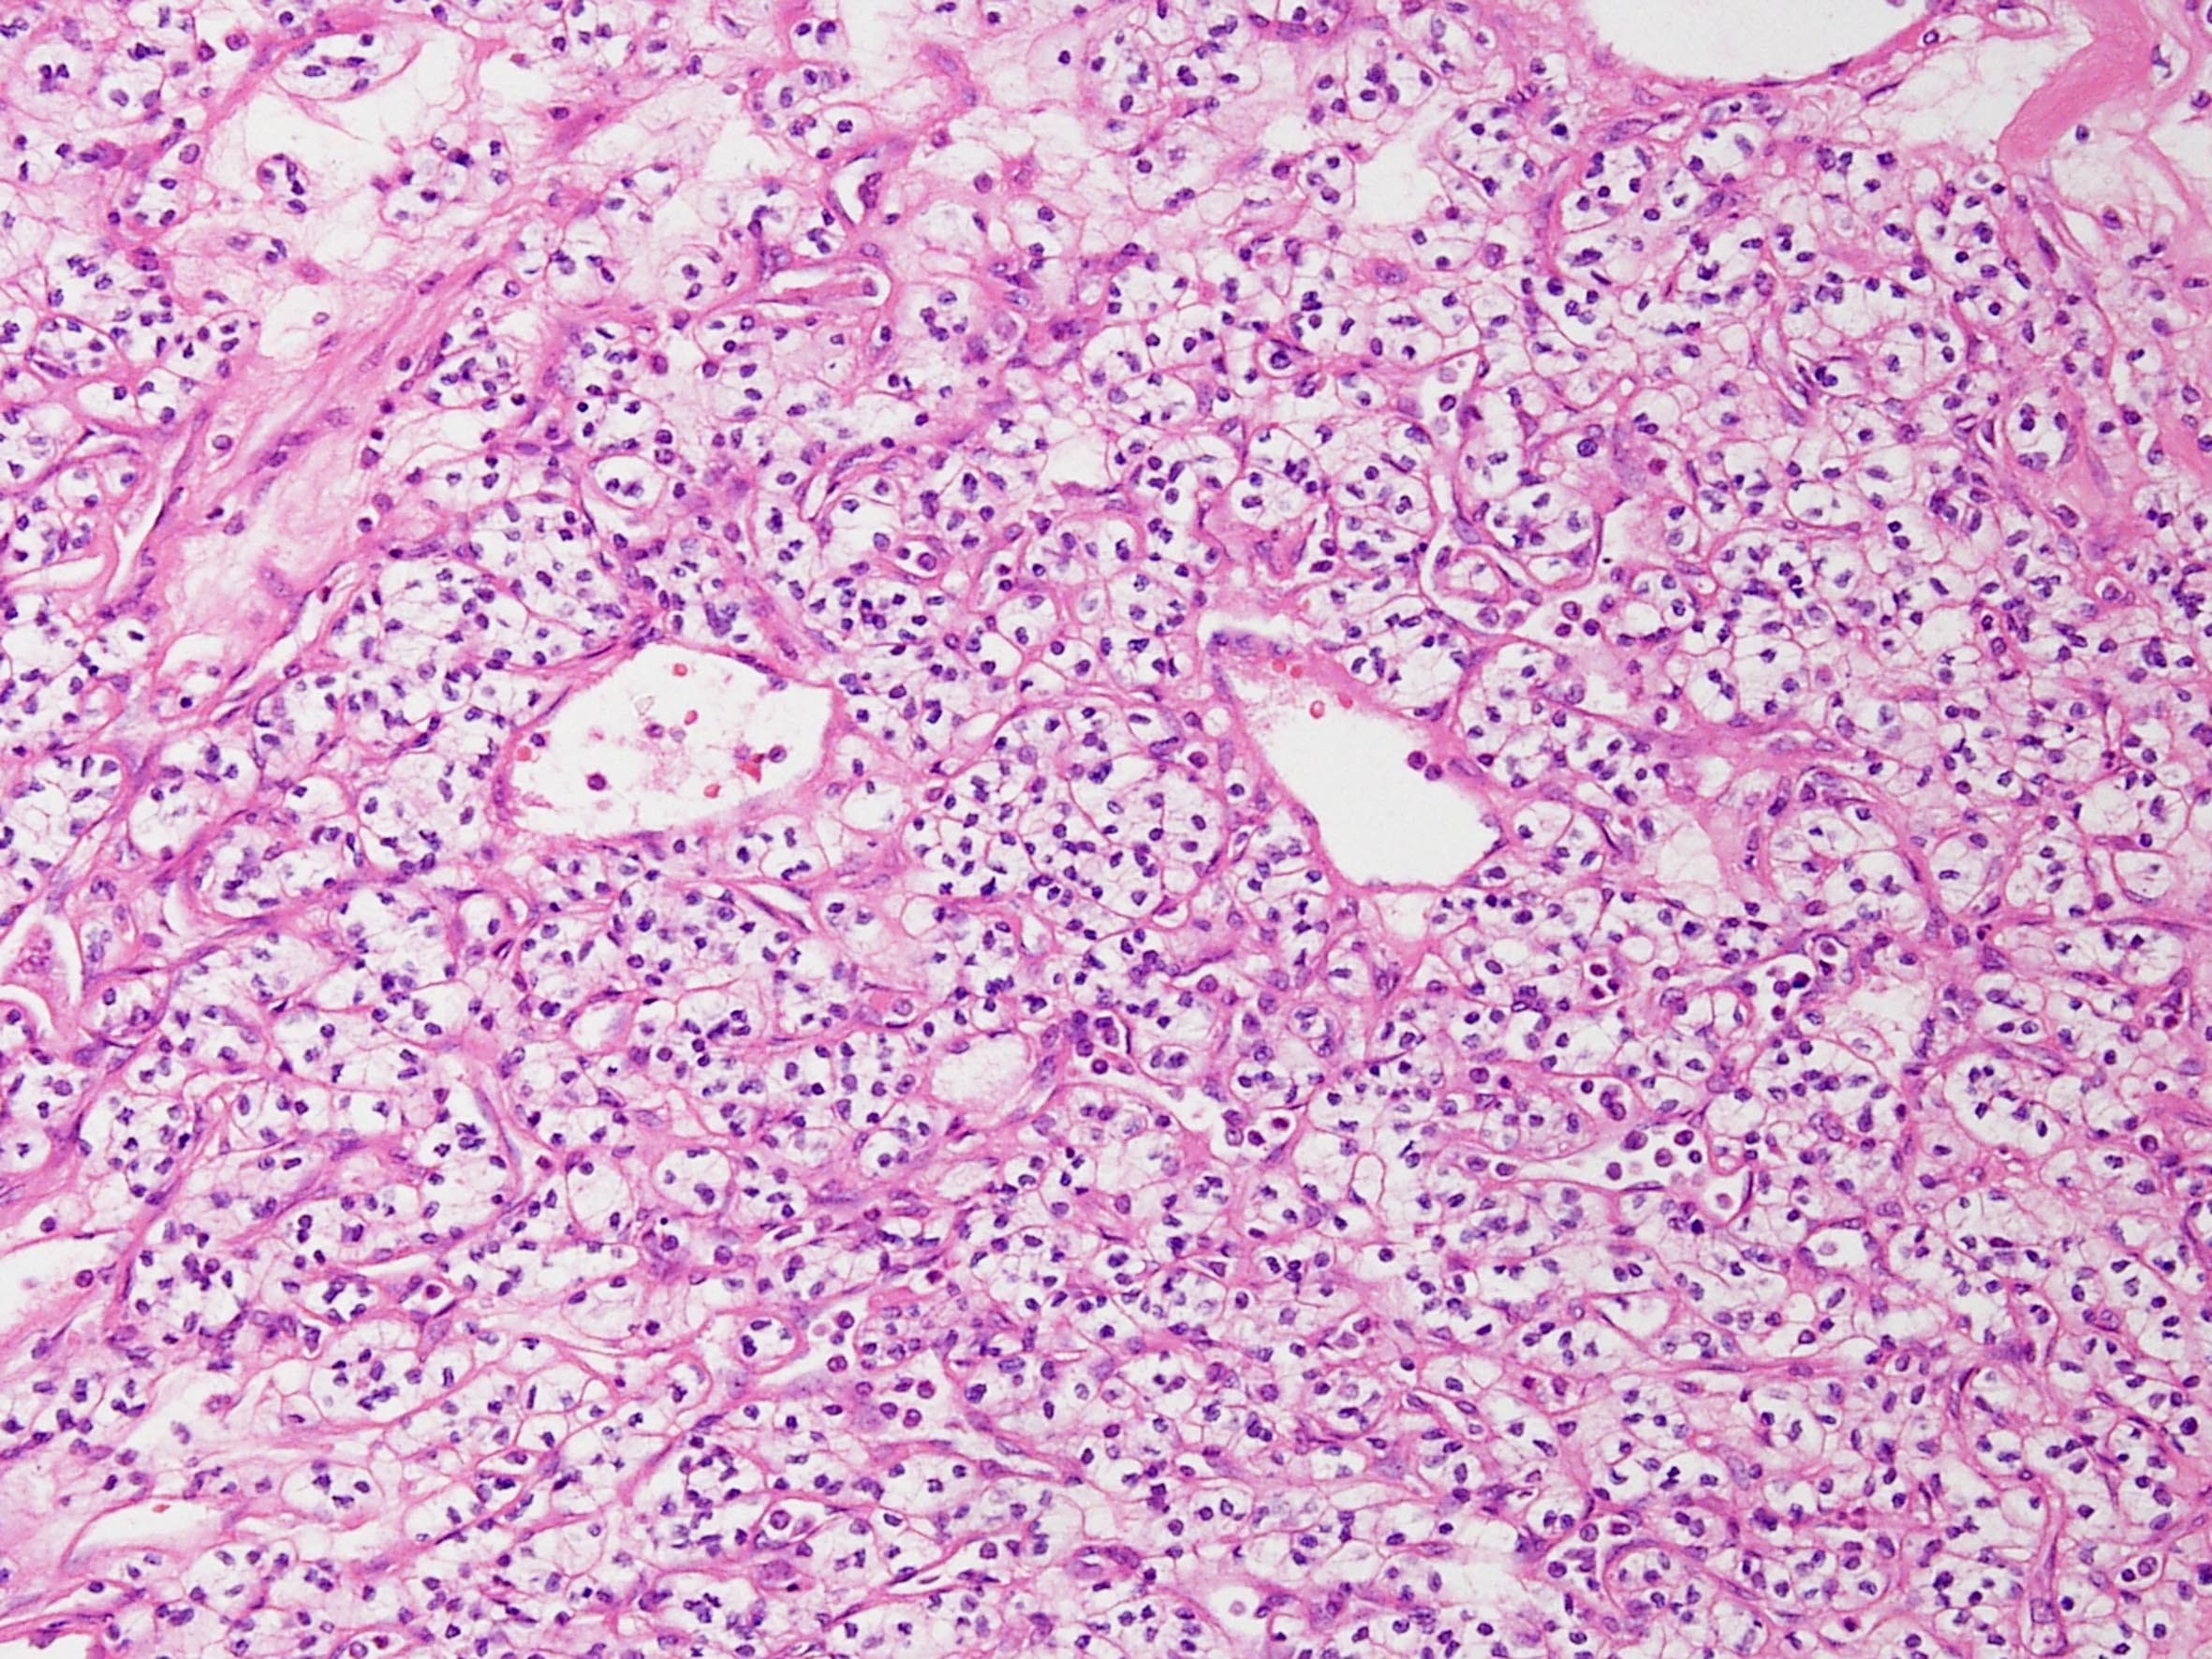

Classification of renal tumors

Case ID: 141